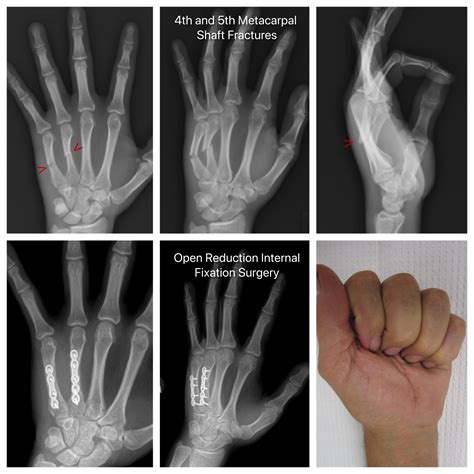

Professional diagnosis is essential to heal a broken finger effectively. A doctor will typically perform a physical examination and request an X-ray to determine the exact location and severity of the fracture. Depending on the type of break, your treatment plan will vary significantly. Common medical interventions include:

• Surgery: In complex cases, such as intra-articular fractures (breaks that extend into the joint), pins, plates, or screws may be required to stabilize the bone.